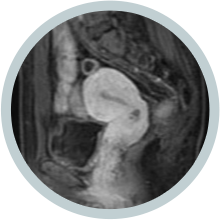

• 시술 진후 시술 직후

하이푸 시술 직후

MRI 조영증강영상에

뚜렷하게 혈류가 차단된

비관류 구역을 보임